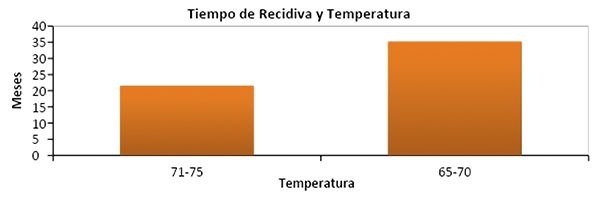

Cuando se analizó el tiempo de recidiva con respecto a cada uno de los grupos se objetivo que el tiempo promedio de recidiva para el grupo de 65°C-70°C fue 35,22 meses (±24,94) y para el grupo de 71°C-75°C fue 21,64 meses (±28,04). No se observó significancia estadística en el análisis de estas variables (p=0,12) (graf. 6).

Gráfico 6: Relación entre temperatura y tiempo de recidiva (p=0,12)

Cuando se analizó el tiempo de recidiva con respecto a cada uno de los grupos se objetivó que el tiempo promedio de recidiva para el grupo de 65°C-70°C fue 35,22 meses (±24,94) y para el grupo de 71°C-75°C fue 21,64 meses (±28,04). No se observó significancia estadística en el análisis de estas variables (p=0,12).